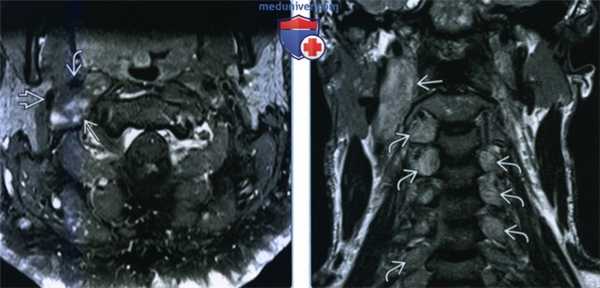

(Слева) МРТ Т1ВИ FS с КУ, пациент с нейрофиброматозом I типа. В сонном пространстве имеется образование округлой формы, неоднородно накапливающее контраст. Внутреняя сонная артерия смещена кпереди. Внутренняя яремная вена уплощена и смещена вперед и в латеральную сторону.

(Справа) МРТ Т2ВИ в коронарной проекции, этот же пациент. Типичная нейрофиброма блуждающего нерва: удлиненная, овальная форма и неоднородный гиперинтенсивный сигнал. Имеются стигмы нейрофиброматоза I типа: множественные опухоли оболочки спинномозговых нервов.